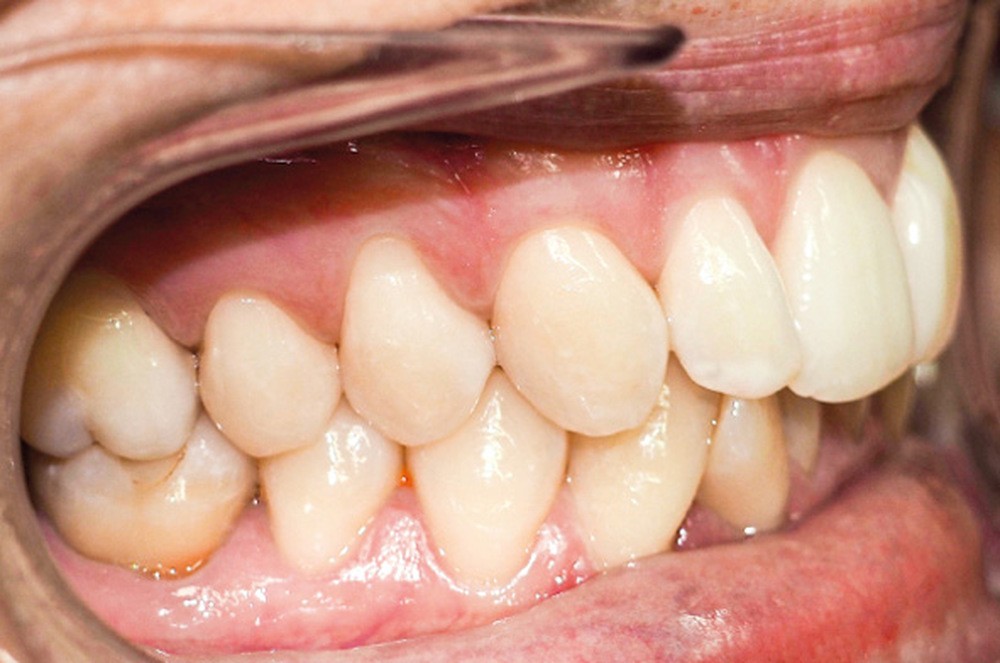

Examen endo-buccal (fig. 2a-e)

En occlusion, on note une relation de Classe I molaire bilatérale avec un surplomb normal et une supraclusion. Les médianes incisives sont concordantes.

Les incisives maxillaires sont de forme triangulaire [1] et l’indice de Bolton est de 97 % qui traduit la présence d’une DDD par excès mandibulaire.